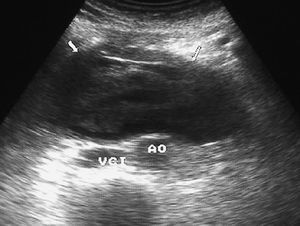

La enfermedad de Crohn afecta al duodeno de forma variable, apareciendo signos radiológicos en un 4% de los pacientes. Se manifiesta como un engrosamiento concéntrico y homogéneo de la pared, que puede producir estenosis de la luz intestinal (fig. 8). La existencia de actividad inflamatoria se identifica ecográficamente como aumento de la vascularización con modo doppler color. En la TC se observa la captación de la pared duodenal con afectación de la grasa adyacente.

Fig. 8--Enfermedad de Crohn duodenal. Corte ecográfico transversal donde se observa un engrosamiento concéntrico de la pared duodenal (D), que respeta la estructura de capas. VCI: Vena cava inferior; AO:aorta.